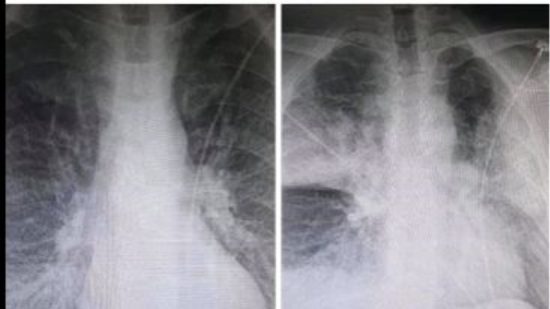

Σχολιάζοντας την ανησυχητική ανάρτηση του ακτινολόγου από το ΚΑΤ, που ανέβασε δύο ακτινογραφίες στο Facebook μέσα από τις οποίες αποτυπώνεται η ραγδαία επιδείνωση που προκαλεί ο κορωνοϊός στους ασθενείς, ο καθηγητής Πνευμονολογίας – Εντατικής Θεραπείας της Ιατρικής Σχολής του Πανεπιστημίου Αθηνών, Θεόδωρος Βασιλακόπουλος, δήλωσε ότι υπάρχουν περιπτώσεις ασθενών των οποίων η καλή εικόνα του αναπνευστικού συστήματος διαρκεί αρκετές ημέρες, αλλά αίφνης την 8η, 9η, 10η ημέρα εκδηλώνουν την επιπλοκή.

«Η ανάρτηση δείχνει μια λοίμωξη του αναπνευστικού, μία πνευμονία, που σε λίγες ώρες μετεξελίσσεται σε μια επιπλοκή της πνευμονίας που ονομάζεται οξεία πνευμονική βλάβη και στη σοβαρότερη μορφή της (ονομάζεται) Σύνδρομο Αναπνευστικής Δυσχέρειας του ενήλικα. Δεν πρόκειται για κάτι σπάνιο στις λοιμώξεις του αναπνευστικού ούτε και στη λοίμωξη που προκαλεί εν προκειμένω ο κορωνοϊός. Εκδηλώνεται και στην εποχική γρίπη και σε άλλες λοιμώξεις. Το Σύνδρομο Αναπνευστικής Δυσχέρειας είναι μία από τις βασικές, σοβαρές αιτίες που θα οδηγήσει κάποιον ασθενή με λοίμωξη σε Μονάδα Εντατικής Θεραπείας (ΜΕΘ). Αλλά και μια από τις αιτίες που ασθενής νοσηλευόμενος σε ΜΕΘ μπορεί να πεθάνει» επεσήμανε ο κ. Βασιλακόπουλος.

Όσον αφορά στη διάρκεια που χρειάζεται για την εμφάνιση της υποξαιμίας, ξεκαθάρισε ότι δεν υπάρχει συγκεκριμένη. «Υπάρχουν ασθενείς που έχουν εμφανίσει την οξεία εικόνα, ακόμη και σε λίγη ώρα, από την στιγμή που εμφανίστηκαν στο νοσοκομείο και υποβλήθηκαν σε ακτινογραφία. Υπάρχουν άλλες περιπτώσεις ασθενών που η καλή εικόνα του αναπνευστικού συστήματος διαρκεί αρκετές ημέρες, αλλά αίφνης την 8η, 9η, 10η ημέρα εκδηλώνουν την επιπλοκή».